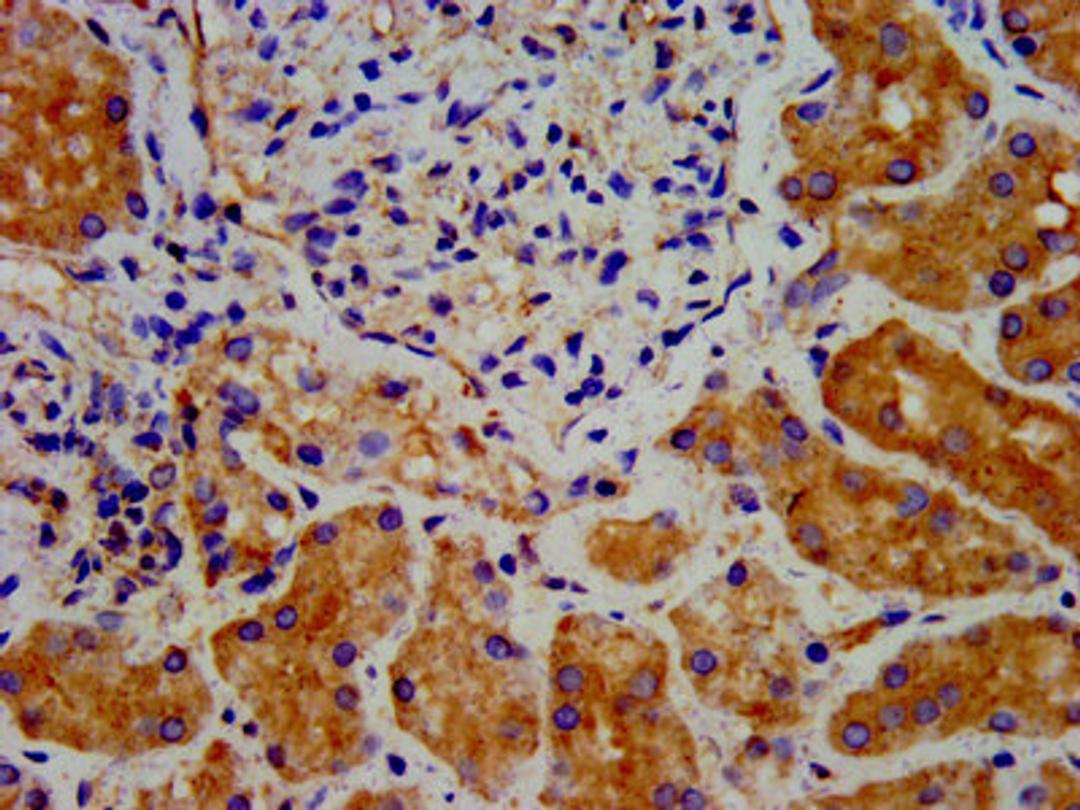

IHC image of CSB-PA822207LA01HU diluted at 1:300 and staining in paraffin-embedded human kidney tissue performed on a Leica BondTM system. After dewaxing and hydration, antigen retrieval was mediated by high pressure in a citrate buffer (pH 6.0). Section was blocked with 10% normal goat serum 30min at RT. Then primary antibody (1% BSA) was incubated at 4°C overnight. The primary is detected by a biotinylated secondary antibody and visualized using an HRP conjugated SP system.